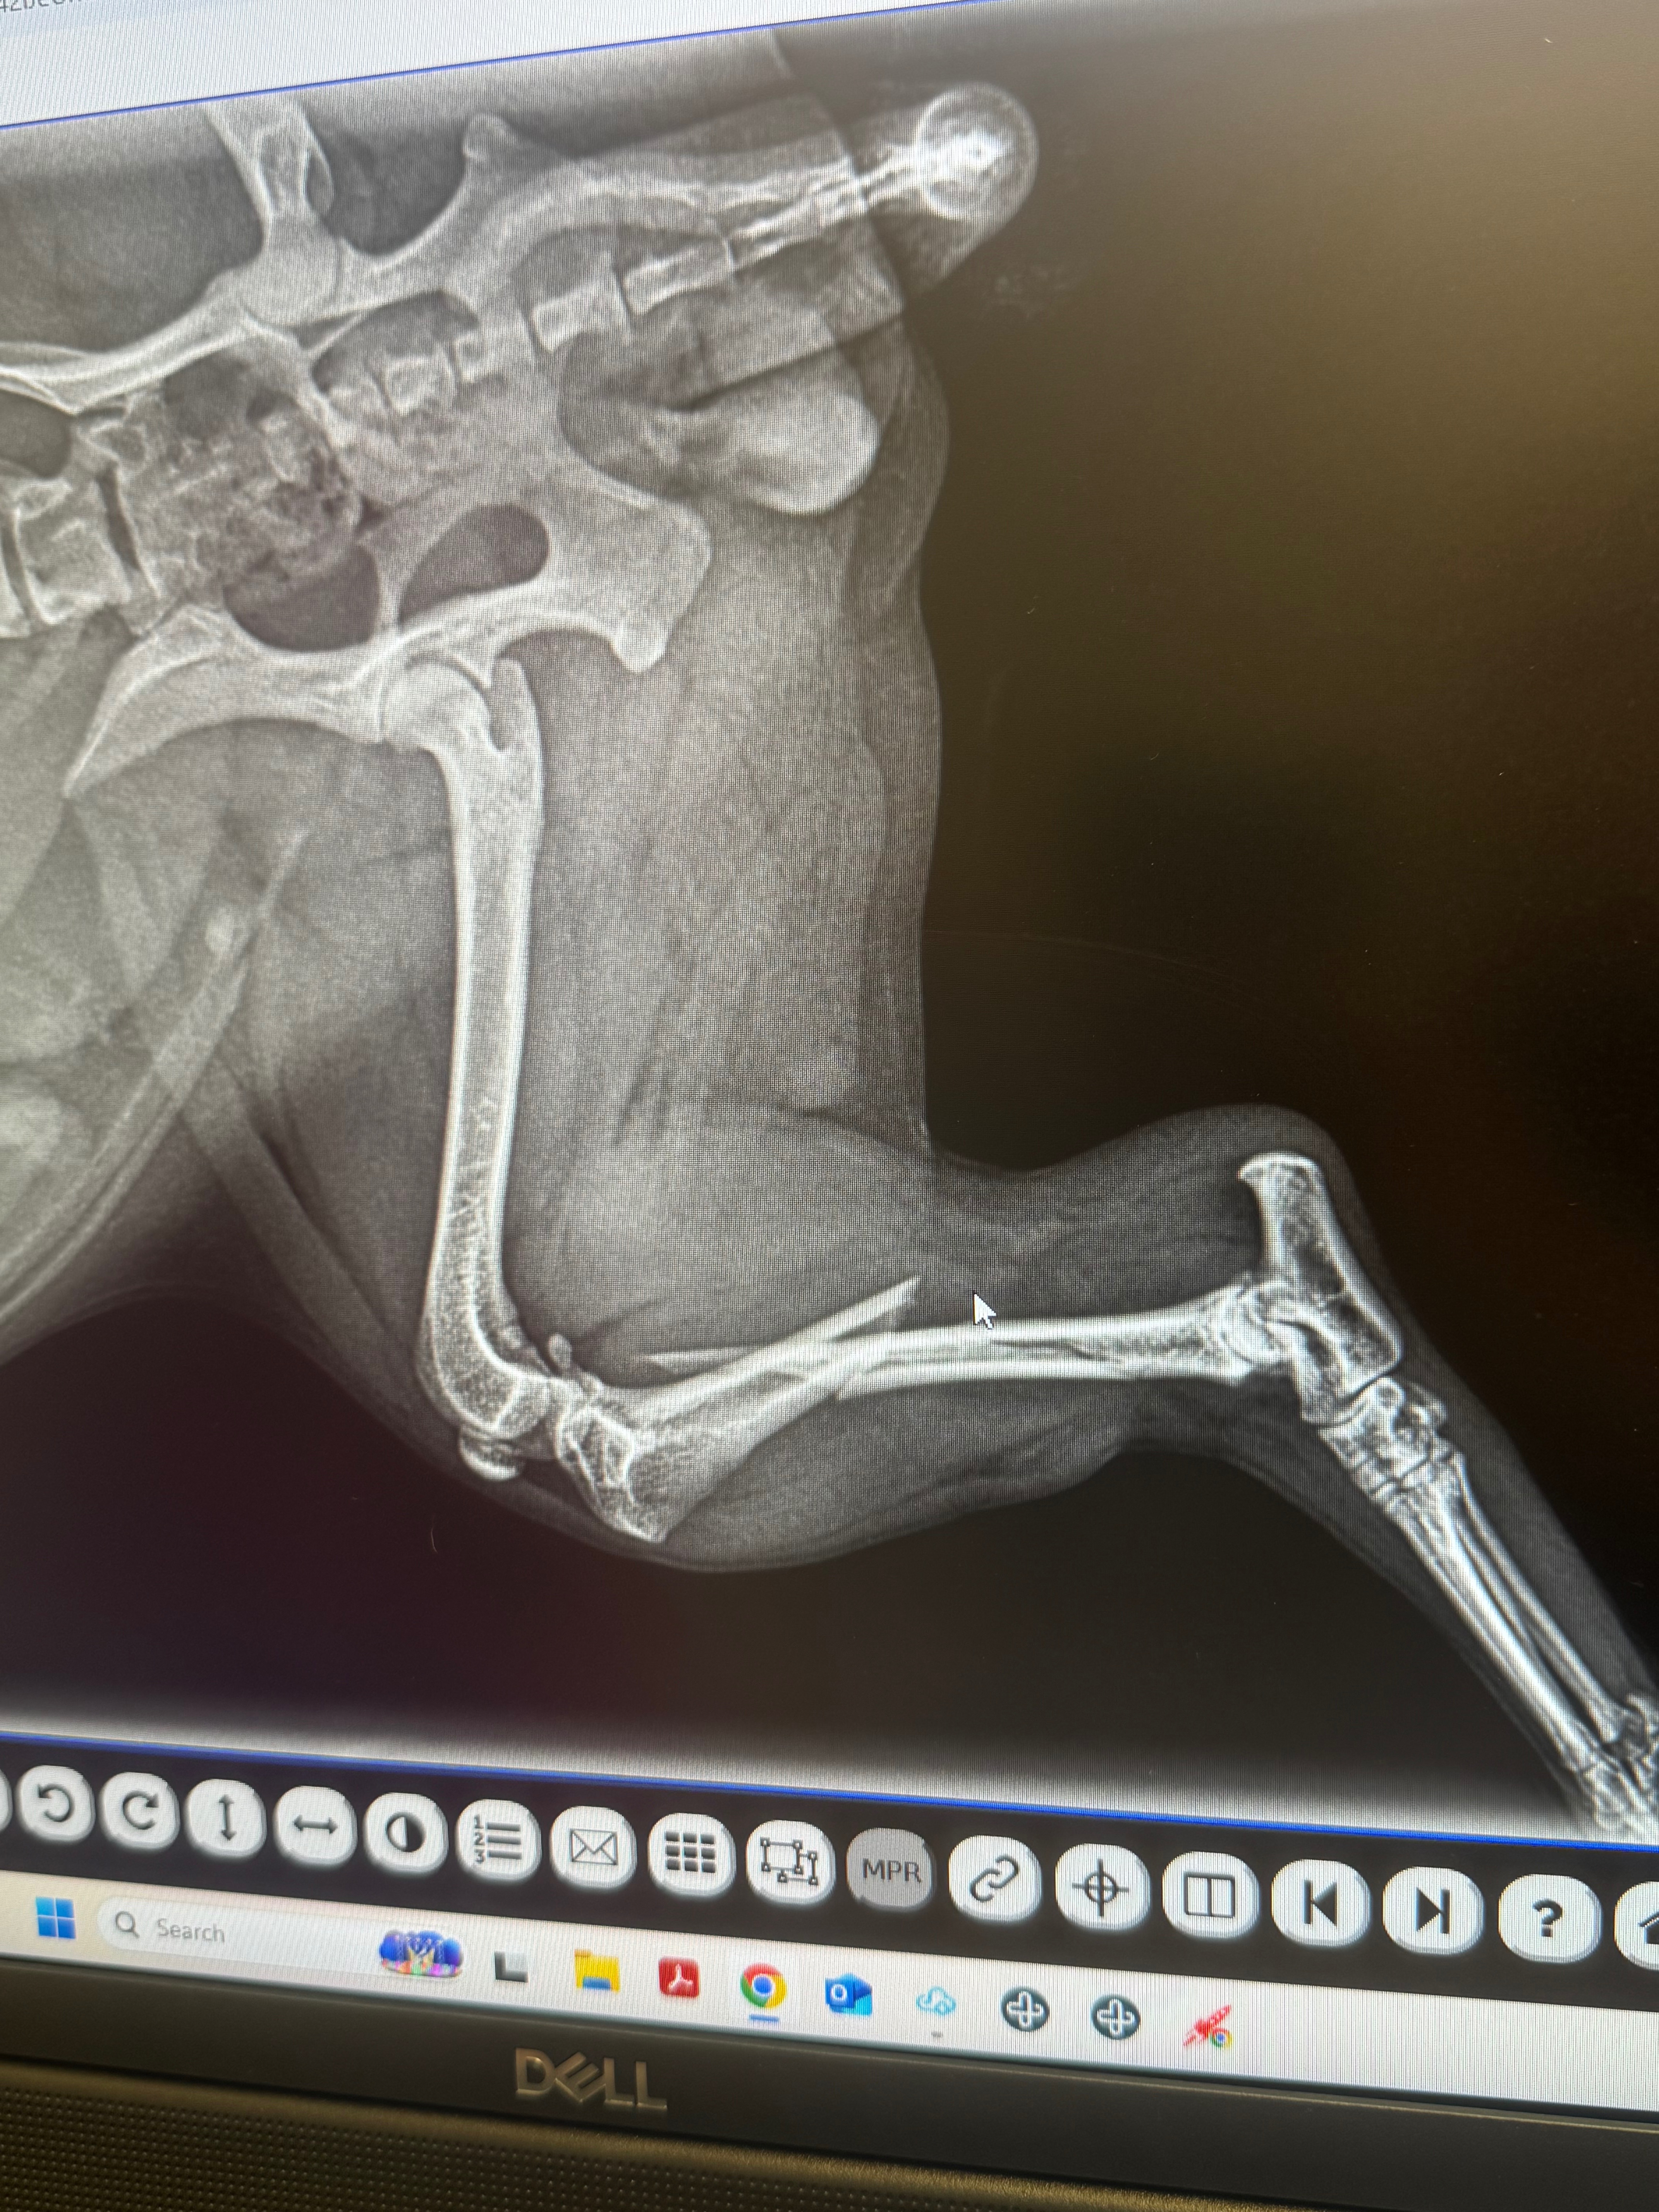

My baby girl has multiple fractures in her leg and needs at least a splint, which was told will not guarantee an actual fix. The orthopedic Surgeon quoted us surgery which will cost 4,925! My husband and I have 3 kids and are already struggling, living paycheck to paycheck.